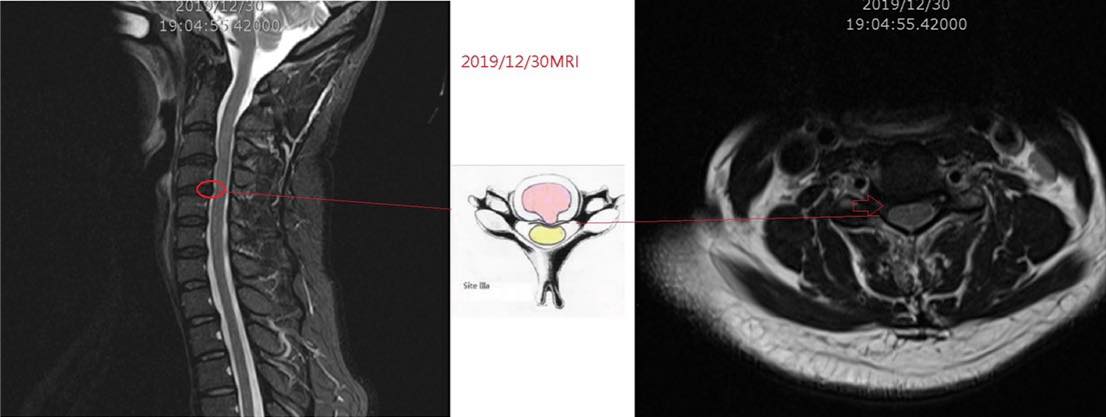

Cervical Spine Treatment Cases 頸椎治療案例 #疼痛三年頸椎病患者親手寫下治療紀錄 #交感神經型頸椎病 #症狀錯綜複雜 2020.10.02 #困擾四年多胸悶手麻頭暈醫案 #一切原因居然是頸椎出問題 #交感神經型頸椎病症狀錯綜... 2020.09.11 #交感神經型頸椎病引起的耳鳴 #耳鳴將近八個月終於得到重大改善 #曾經耳鳴到無法睡覺... 2020.08.22 #感謝板橋蘇先生熱情見證 #神經根型頸椎病卡壓 #曾痛痛到左手無法騎單車撥桿 #麻脹刺... 2020.08.04 #後縱韌帶鈣化引起椎管狹窄 #痛到完全無法睡覺長達半年以上 #原本已經準備開刀最後逆... 2020.07.16 #牽一頸而動全身的特殊醫案 #兩分鐘瞭解交感神經型頸椎病 #絕望的黑暗人生看到一絲希... 2020.07.03 #長達七年的頸椎疼痛是怎麼回事 #神經根型頸椎病 #低頭族跟家庭主婦辛苦了 #逆轉勝醫... 2020.07.01 #頸椎整合中醫微創療法 #感謝新竹黃大哥熱情見證 #逆轉勝成真醫案 2020.06.25 #頸椎病手術後也要要好好保健 #毛巾操很重要再度上場 #感謝某大醫學中心主任見證 2020.06.24 #這些症狀很可能都是頸椎出問題 #患者看七種不同科別醫師找不出原因 #交感神經型頸椎... 2020.06.09 #消失的頸椎曲線能夠回來嗎? #核磁共振前後對比椎管容積打開 #脊椎整合中醫微創療法❤... 2020.06.05 #感謝新竹薛大哥熱情見證 #頸椎整合中醫微創療法 治療:4/21~5/30(八次) 效果顯著... 2020.05.30 從宜蘭來的游小姐患者熱情見證 頸椎整合中醫微創療法 逆。轉。成。真。 2020.05.29 #脊髓型頸椎病案例 2020.05.26 #感謝新北市黃小姐熱情見證 #疼痛時間超過一年 #晨起麻痛到不行的日子長達半年以上 #... 2020.05.16 ← 上一頁 5 6 7 8 9 下一頁 →